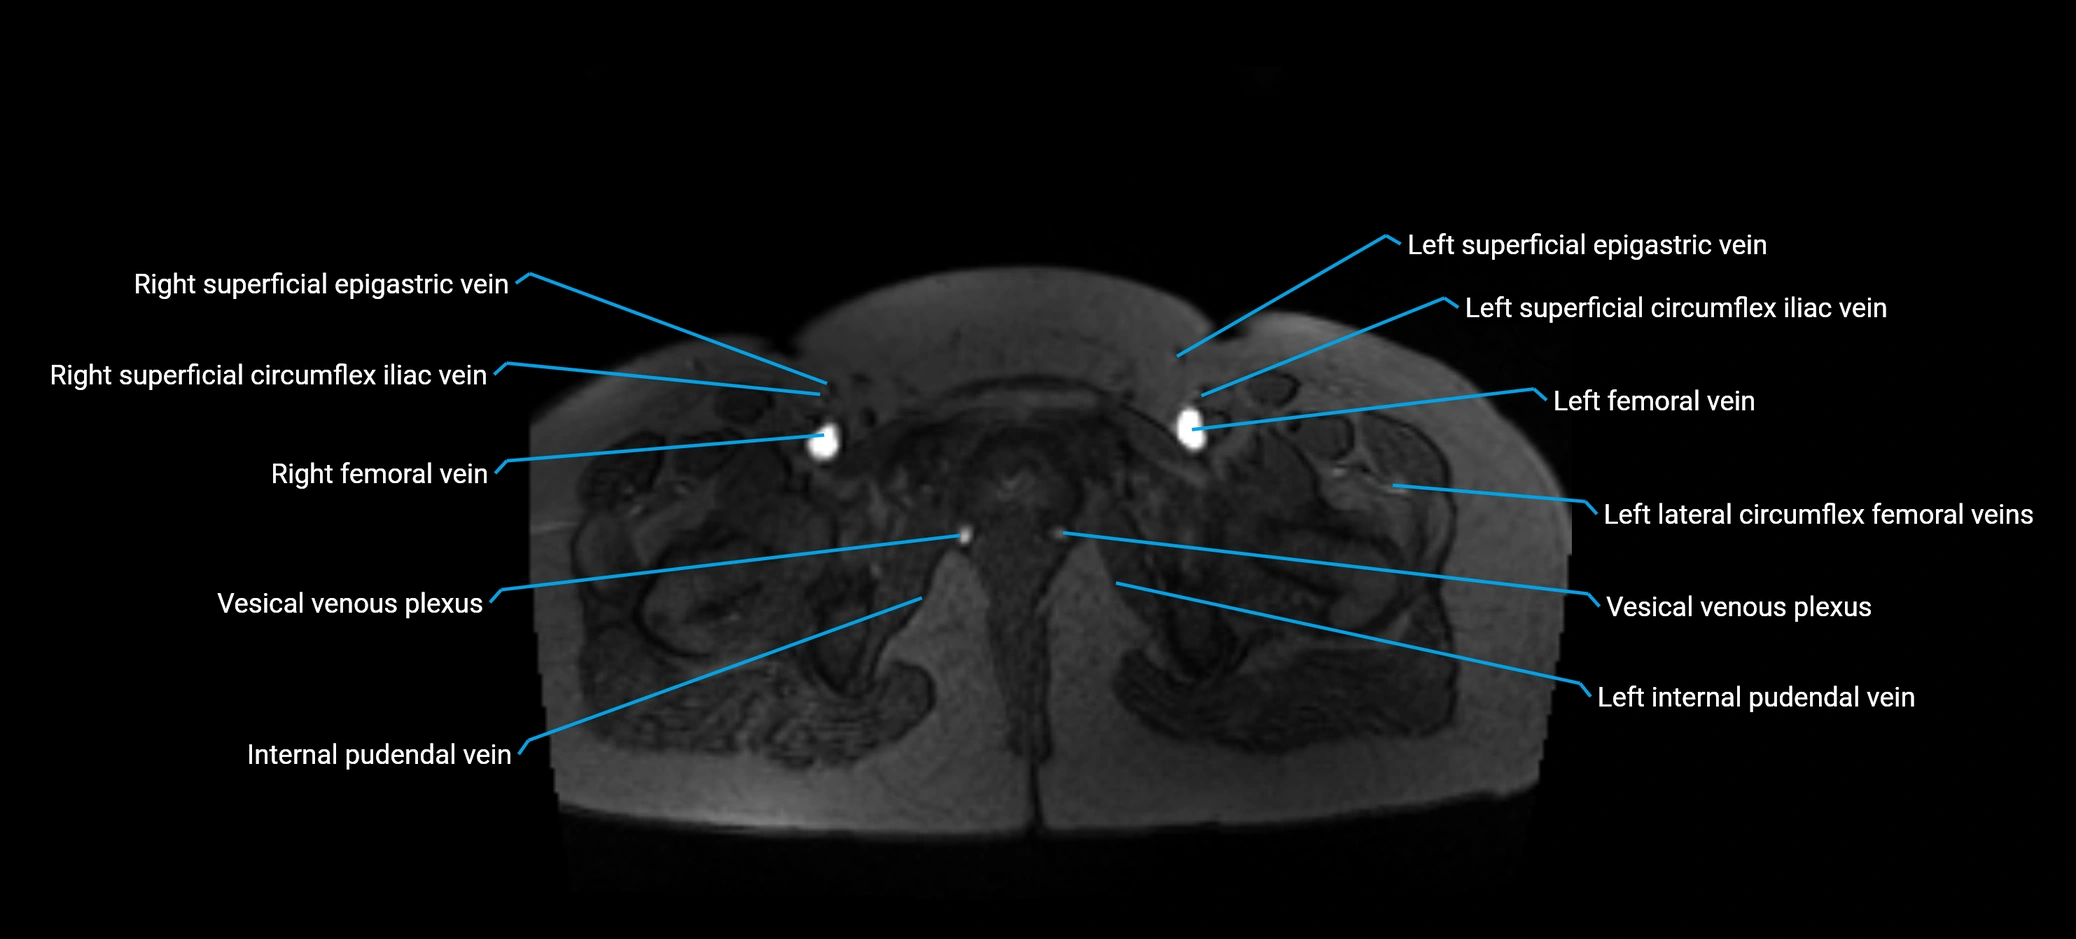

MRI image

image